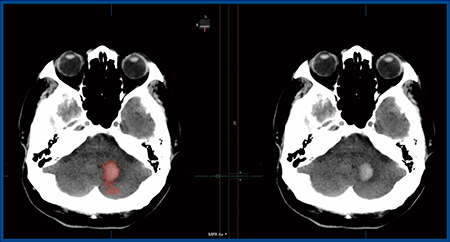

Hemorrhage analysisでは,頭部単純CT画像から出血領域を抽出して強調表示する(図2)。脳出血はCTでは高吸収域となり,比較的診断がしやすい画像を示すが,tPA静注療法の適応判断において出血を見逃すことはリスクが大きいことから,アプリケーションで脳出血の有無を確認できる意義は大きいと考えられる。

図2 Abierto RSSのHemorrhage analysis